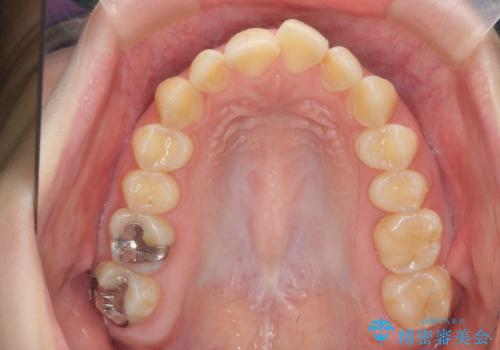

マウスピース矯正で行う出っ歯の治療

- 飛び出したように見える前歯の改善を求めて来院されました。

元々、セラミッククラウンですぐに歯並びを改善したいと希望されていましたが、目立たないマウスピース矯正治療のご提案を行なったところ矯正治療による歯並びの改善を選択されました。

矯正治療を行ったことで出っ歯の改善とともに安定した噛み合わせも手に入れることができました。